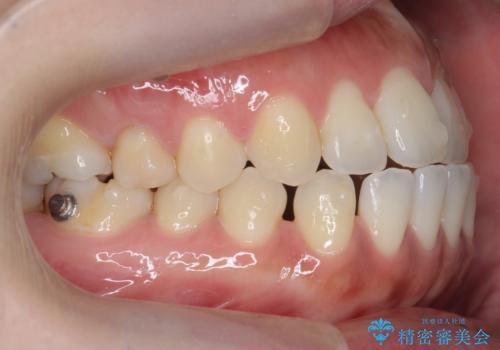

受け口、すきっ歯を インビザラインで モニター治療

- 前歯のすき間と受け口を気にして来院。

マウスピースでしっかり閉じています。

下の前歯を後方に移動するため、ゴムを上下のマウスピースにかけてもらいました。